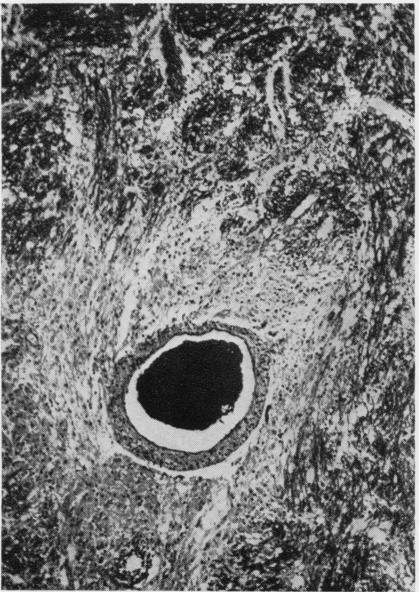

The clinical and pathological findings are described of a fatal case of acute haemorrhagic leucoencephalitis and disseminated encephalomyelitis with acute necrosis of the white matter of the spinal cord. It is suggested that the reaction was a severe immunological response of an allergic nature, probably due to antitetanus serum.